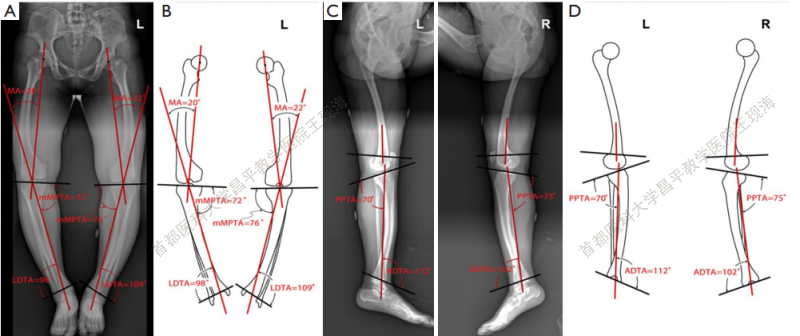

以负重全长片为指标,测量冠状面和矢状面畸形(图2)。下肢的关节角如表1所示。

图2 在冠状面和矢状面上测量的关节方向角。(A)冠状面的X线;(B)冠状面下肢轮廓;(C)矢状面X线图;(D)矢状面下肢轮廓。

下肢外观有所改善。CORA的平均位置如下:左侧在膝关节方向线上17厘米,右侧在膝关节方向线上12 cm。畸形的评估修正,MPTA改善,左侧由76°-到87°,右边由72°到 96°(Figure 4A,B and Table 2) 。mLDTA,左边从109°到 101°,右边从98°到90°(Figure 4A,B and Table 2) 。

图4在冠状面和矢状面测量的术后关节方向角。(A)冠状面X线;(B)冠状面下肢轮廓;(C)矢状面X线;(D)矢状面下肢轮廓。

矫正后的双侧力线较术前均明显改善(表 2) 。在最后一次就诊时,PPTA和ADTA接近正常值,得到了明显的矫正(图 4C,D, 表 2) 。在上次访问中,双侧骨质均已愈合(图 5) 。